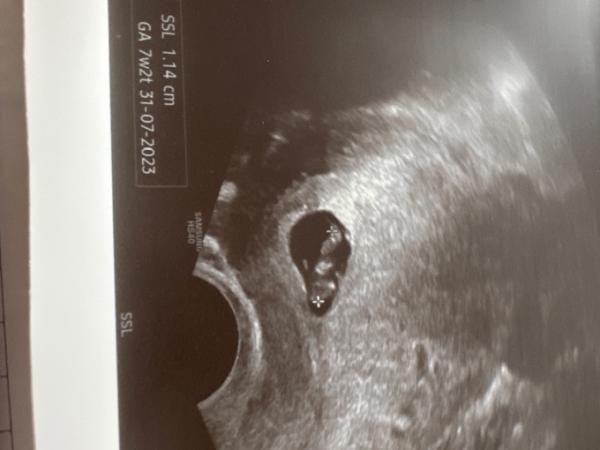

Hallo ihr lieben, ich komme gerade vom Frauenarzt. Laut ES bin ich heute bei 8+1. Der Frauenarzt konnte einen Herzschlag sehen aber der Ebryo war SSL nur 1,14 cm groß. Eigentlich müsste er doch schon doppelt so groß sein? Laut US Gerät bin ich bei 7+2. Der FA meinte ich hätte falsch gerechnet aber das habe ich nicht. Er hat mir gar nicht zugehört und mich gar nicht ernst genommen. Habt ihr Erfahrungen? Kann trotzdem alles gut gehen?

Bild zu Embryo zu klein - Schwanger - wer noch? Rund um die Schwangerschaft